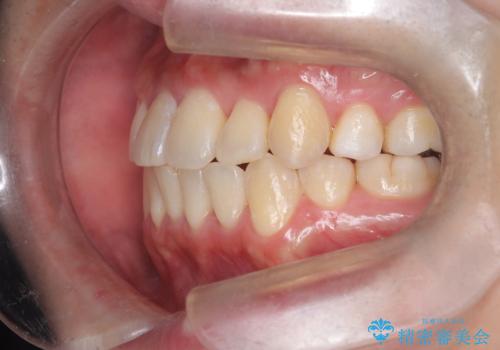

【重度叢生ワイヤー矯正】きれいな歯並びにしたい

- きれいな歯並びにしたいとの希望を持って来院された患者様です。

上下左右小臼歯を抜歯する治療計画を立て審美装置にて治療を行いました。

骨格的3級傾向もあり、咬合関係を仕上げるのに時間がかかりましたが、患者様には大変満足していただけました。

難しいケースでしたが、矯正用アンカースクリューを用いながら、臼歯関係もきれいに仕上げることができました。